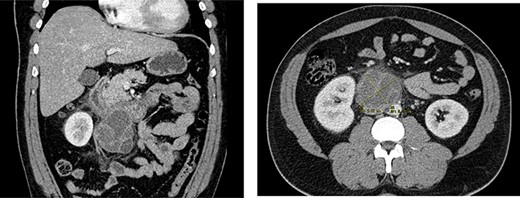

After this diagnosis, the patient was re-evaluated, maintaining a normal testicular examination; tumour markers where rechecked: β-hCG 243 U/L, α-fetoprotein (AFP) 2.06 ng/mL and lactate dehydrogenase (LDH) was normal; sonography identified right testicle heterogeneity with a nodular hypoechoic area with internal calcifications (Fig. 3) and thoracic CT showed no relevant abnormality.

Scrotal ultrasound with a heterogeneous nodule with microcalcifications.